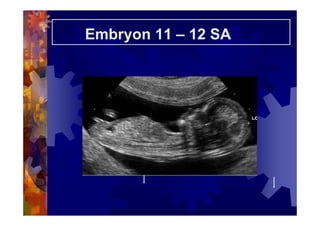

Embryon 11 – 12 SA

ECHOGRAPHIE DE DATATION

Longueur cranio-caudale

: Valeurs normales

( Robinson HP, Fleming JE British journal Obstet.

Gynaecol. 1975 ;82,702-10)